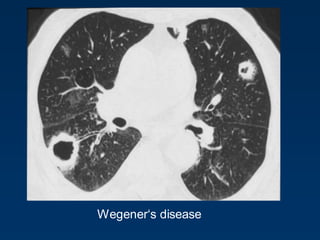

Wegener„s disease

Rheumatoid Arthritis

Emphysema